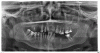

Svetaka Опубликовано 3 октября, 2012 Поделиться Опубликовано 3 октября, 2012 2 недели назад, упав с тротуарного бордюра, я лишилась 4 передних зубов (один вылетел с корнем, два из трех оставшихся корней сильно качаются, и их тоже придется удалить, а последний корень стоит, кажется, прочно). Доктор клиники, куда я обратилась по поводу возможности протезирования на имплантатах, по результатам осмотра и на основании панорамного снимка вынес вердикт: прежде чем решать проблему протезирования необходимо удалить все зубы, кроме 45, 44, 43 и 13. Причина - из-за пародонтита или периодонтита произошло рассасывание кости вокруг корней зубов, зубы стали подвижными (2 ст. подвижности) и в скором времени выпадут сами.На следующий день врач другой клиники подтвердил, что зубы действительно практически не в кости, но те, которые более-менее устойчивые (в основном внизу), можно пока не удалять, а укрепить путем шинирования. Это даст отсрочку на какое-то время. Обязательными к удалению зубы, помимо передних, считает 16 (корень практически ни на чем не держится), 23 (подвижен существенно), 26 (перфорация, Pt + штифт между корнями), 36 (корень, но он мало подвижен) и 46 (подвижность III ст). Удаление 27 (штифт установлен не в то место) под вопросом. Все равно получается, что верху зубов практически не останется. Уважаемые доктора. Я в отчаянии. Посоветуйте, пожалуйста, что делать? Можно ли сохранить какие-то из «приговоренных» к удалению зубов? В частности 26 с 27 + корень 11 и подвижный 23. Готова к длительному лечению.И главное, какие ВАРИАНТЫ ПРОТЕЗИРОВАНИЯ ВЕРХНЕЙ ЧЕЛЮСТИ (КРОМЕ СЪЕМНОГО) возможны в моей ситуации? Я так понимаю, что в самом лучшем случае вверху останется 5 зубов слева (23-27) + справа один полноценный (13) и один корень (11), а в худшем случае там останется всего 3 зуба - 13, 24 и 25.Сразу скажу, что установку большого количества имплантатов я просто не выдержу. Точно знаю. Слышала про технологию протезирования на имплантатах «all-on-four». Но я так поняла, что она применяется при полном отсутствии зубов.Подскажите, пожалуйста, в каком направлении двигаться.Может, кто-то порекомендует опытного врача в Москве, у которого можно проконсультироваться. С уважением, Светлана (45 лет, г Москва).Зубная формула.doc 1 Ссылка на комментарий

Sahan Опубликовано 4 октября, 2012 Поделиться Опубликовано 4 октября, 2012 На верхней действительно все удалять и проводить имплантацию,клыки оставить на время интеграции имплантатов для временной конструкции, а после интеграции их тоже удалить , на их место поставить имплантаты и сразу же нагрузить в связке с остальными имплантатами. Или удалить все кроме клыков и изготовить частичный сьемный протез с опорой на клыки.На нижней челюсти удалять 35,42,47,48. За остальные можно побороться. Кюретаж, затем протезирование. В область отсутствующих зубов или имплантаты или чсп. Ссылка на комментарий

Svetaka Опубликовано 23 октября, 2012 Автор Поделиться Опубликовано 23 октября, 2012 На прошедшей неделе посетила трех врачей, с большим опытом работы в области имплантации. 1й доктор (порядка 25 лет занимается только имплантацией) сказал, что случай у меня очень сложный. Протезирование на имплантатах считает возможным по такой схеме: удаление зубов (практически всех), после заживления десен серьезная пародонтологическая подготовка, затем внизу костная пластика (местами мало кости для установки имплантатов + нижнечелюстной нерв близко), вверху синус-лифтигн, имплантация … Сказал, что лечение сложное, долгое и дорогостоящее, а предсказать результат (срок службы имплантатов) в данном случае невозможно. Полагает, что после обязательного удаления безнадежных зубов можно было бы год-два попользоваться съемными протезами, а потом вернуться к вопросу протезирования на имплантатах. За это время волнообразный рельеф кости в некоторых местах мог бы выровняться (это важно, как я поняла, не только из эстетических соображений). 2й врач (стоматолог-универсал, но установил более 3000 имплантатов) сказал, что проблем особых не видит. Предлагает такой вариант: операция по удалению всех зубов внизу и вверху + одномоментно в позиции удаленных зубов устанавливает вниз 6 имплантатов под металлокерамические коронки (мост на 12 зубов), вверху на 4 имплантата поставит две балки (по одной на двух имплантатах слева и справа) для фиксации ПСП. Кажется, под общей анестезией (сказал, что я буду спать). Заверил, что имплантаты прослужат всю оставшуюся жизнь. 3й доктор (челюстно-лицевой хирург, имплантолог, стаж 27 лет) считает, что протезирование на имплантатах возможно, но рекомендует начать с простого варианта - съемные протезы. При этом считает, что нужно удалить не все, а лишь разрушенные и сильно подвижные зубы. По мере потери зубов заменять ЧСП на новые, а при полной потере уже рассматривать варианты протезирования с применением имплантатов. Уверяет, что к тому моменту существенной атрофии кости под ЧСП и оставшимися зубами не произойдет.Лично у меня 2й вариант вызывает некоторые опасения по поводу слишком обширного оперативного вмешательства (в один прием удаление 22 зубов + установка 10 имплантатов, балок …) и одномоментной установки имплантатов в места удаленных зубов, у которых было и, наверное, есть воспаление околозубных тканей + настораживает уверенность врача в неограниченном сроке службы имплантатов (данное заключение не могло быть сделано на основе его практики, поскольку сам он ставит имплантаты всего лишь лет 10).Подходы 1го и 3го по сути очень похожи - начать со съемных протезов. Разница лишь в том, что последний предлагает сохранить большее количество зубов. Решение он принял, не видя снимка, по результатам осмотра. Сказал, что некоторые зубы стоят как вкопанные, и удалять их пока не надо. Это совпадает и с моим желанием, но пугает то, что многие специалисты на этом форуме (да и пародонтолог на приеме) считают, что вылечить уже ничего нельзя, а «сохранение таких зубов влечет за собой потерю костной ткани, которую пока еще можно использовать для имплантации».Уважаемые специалисты, прокомментируйте, пожалуйста, рекомендации врачей и помогите принять правильное решение. Очень боюсь совершить ошибку. Ссылка на комментарий